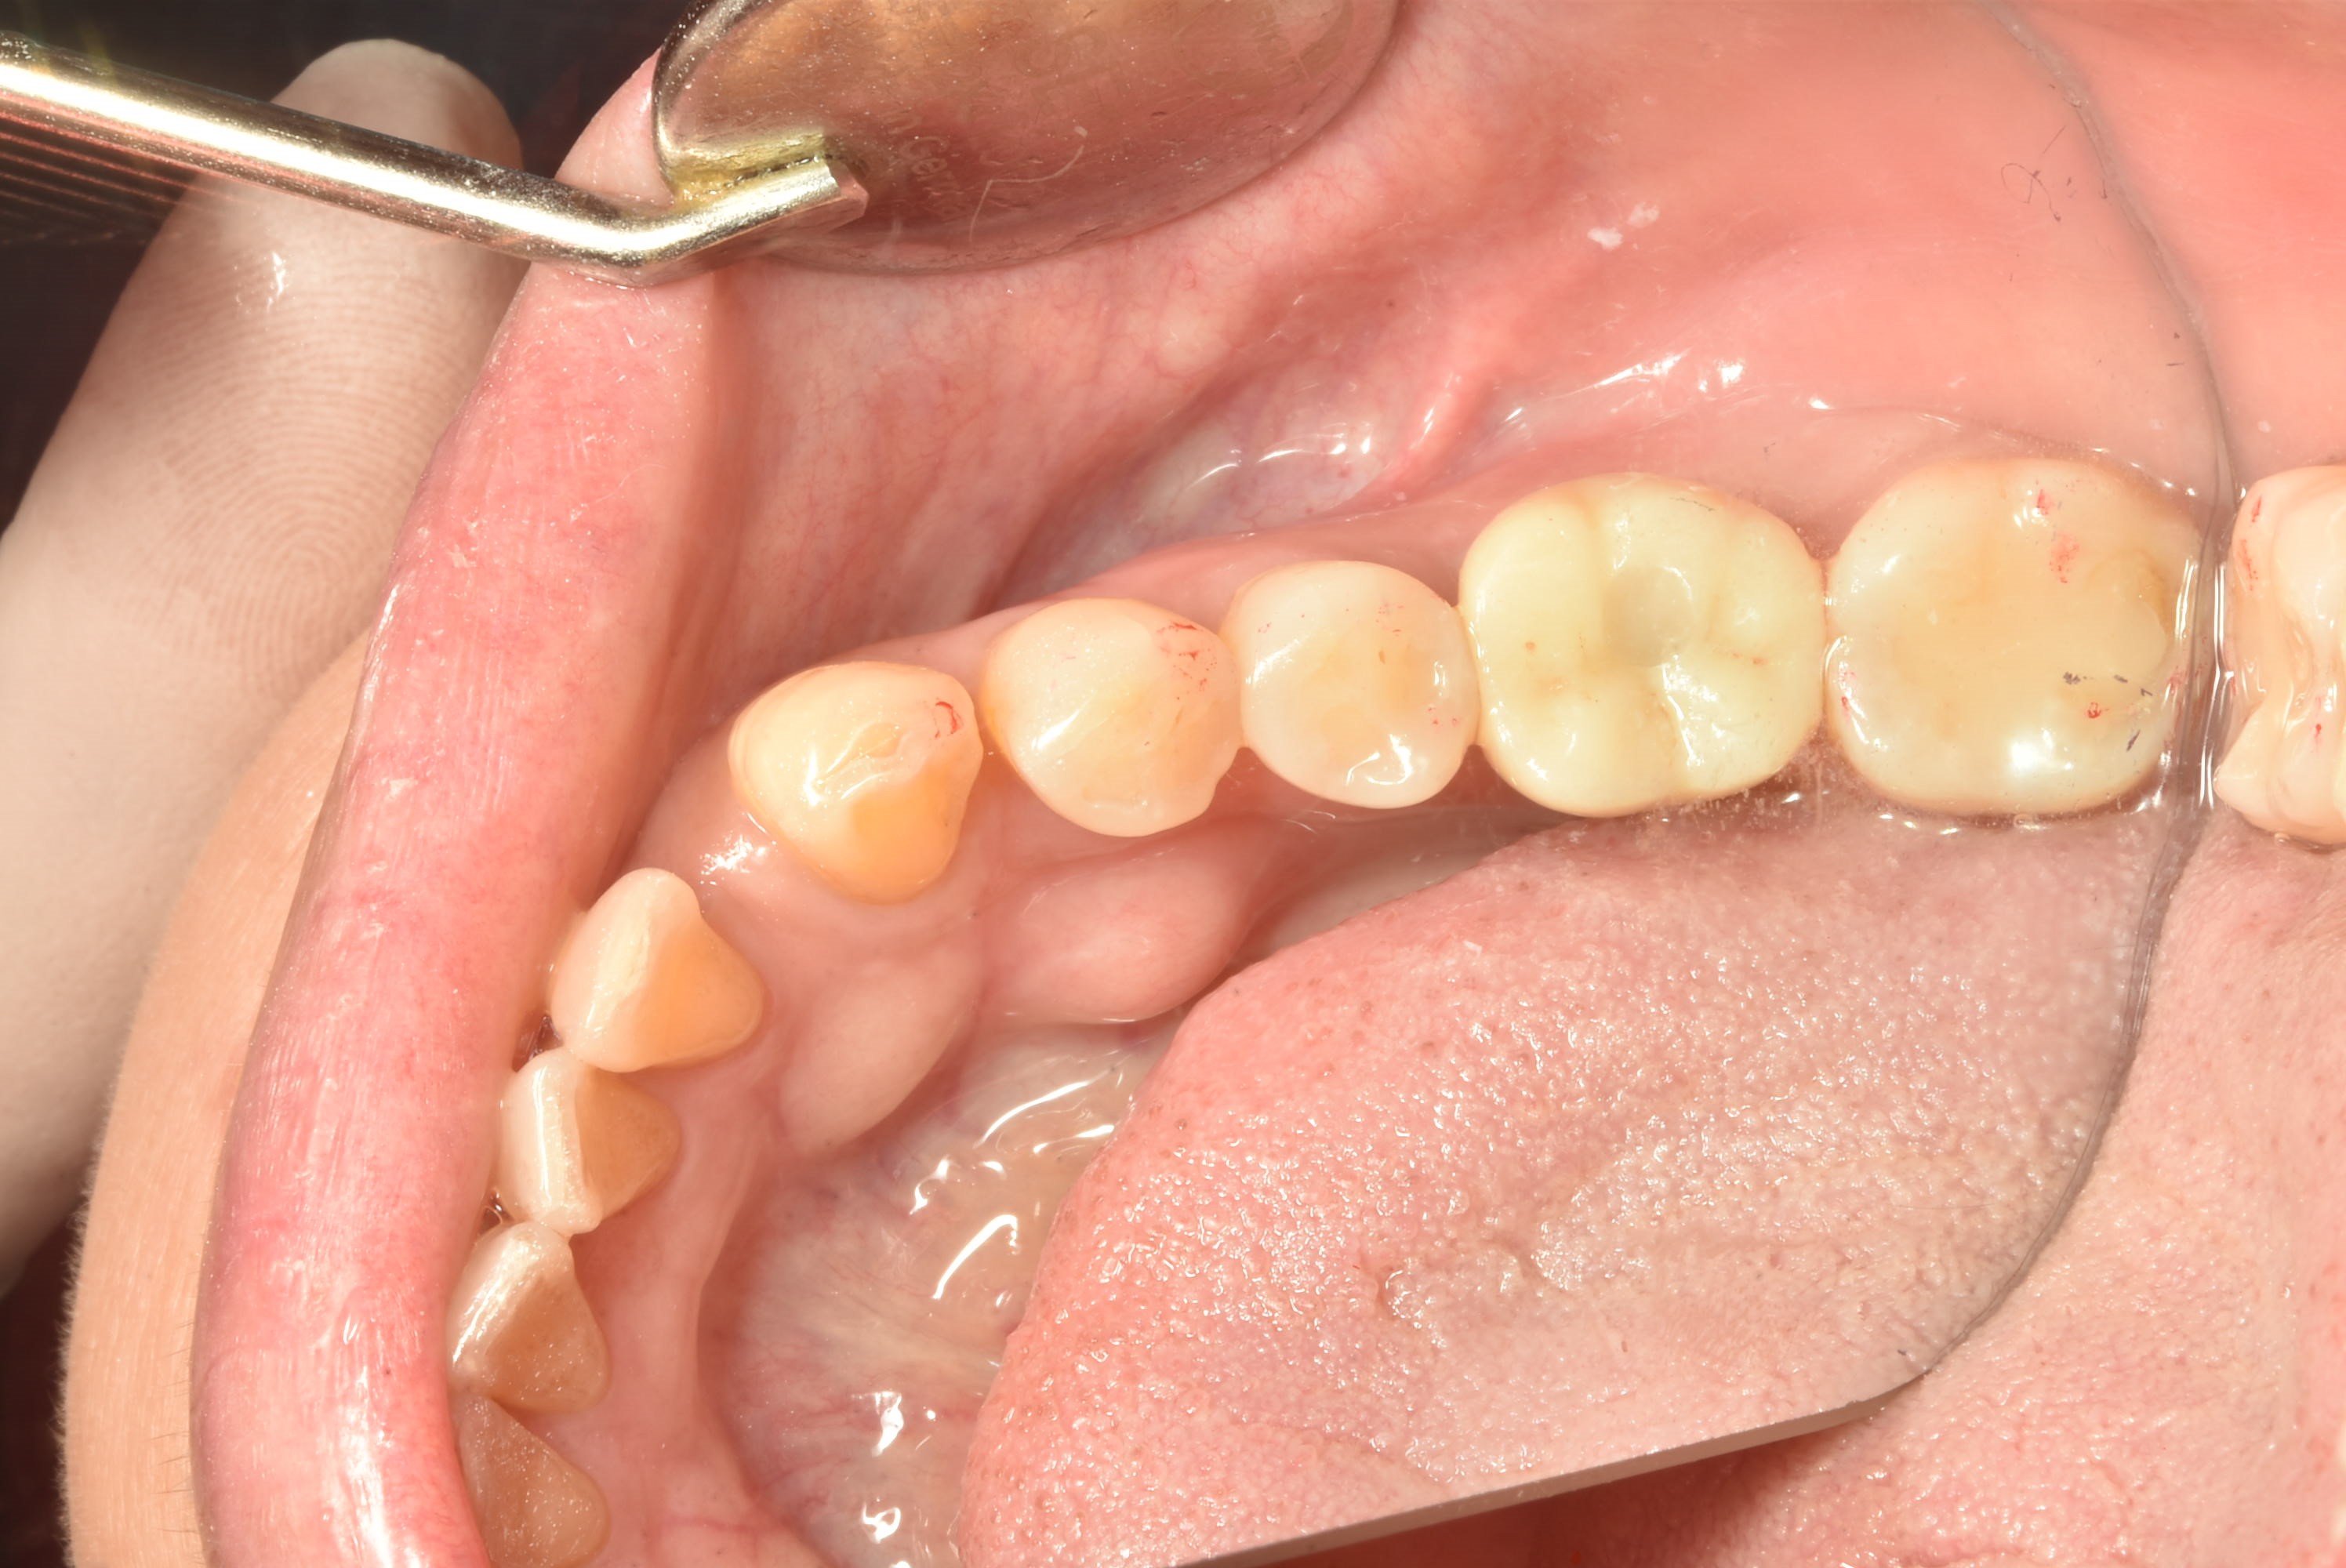

案例三

立即拔除牙根不好的牙齒

立即植入植體

鎖上癒合螺帽

2-3個月癒合,7-10天完成假牙 ,試戴、調整咬合高度並鎖上,封填,完成